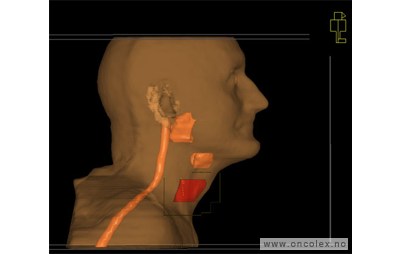

Bildeeksempler

• 70 Gy til svulsten (GTV)

• 46 Gy til eventuelt mikroskopisk sykdom (ITV)

• Samtidig gis boost 6 ganger i uken

• Alle felter skal behandles ved hver fraksjon.